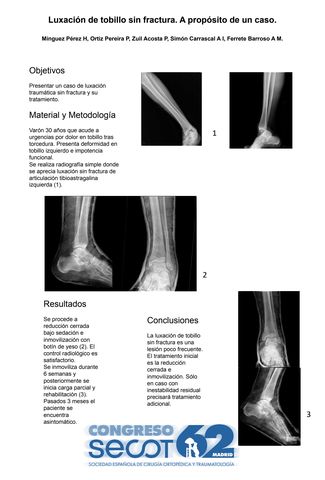

Luxación de tobillo sin fractura. A propósito de un caso.

HILARIO MINGUEZ PEREZ, PALOMA ORTIZ PEREIRA, PATRICIA ZUIL ACOSTA, ANA ISABEL SIMÓN CARRASCAL, ANA MARIA FERRETE BARROSO